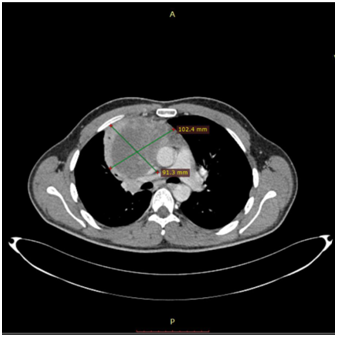

Bild 4 CT – axial plan demonstrating a 10cm Yolk sac tumor invading the truncus pulmonalis and the vena cava superior.

The 1st case we report is of a 22-year-old Caucasian male, who was admitted to our hospital with a 3-days history of progressive dyspnea on exertion, neck swelling, fatigue, persistent chest pain, pyrexia, and a cough that was occasionally productive of blood. The physical examination revealed a heart rate of 115 beats per minute (Sinus Rhythm), a respiratory rate of 25 breaths per minute and superficial vascular distention over the neck. Laboratory studies revealed elevated serum α-fetoprotein (AFP) (5380 IU/ml) and D-dimer (481ng/ml). A chest X-ray in the poster - anterior view, upon admission, depicted a suggestive right upper mediastinal mass (Bild 1). Radiography was followed by contrast-enhanced CT scan that revealed a large, homogeneous mediastinal mass crossing into the anterior mediastinum and compressing – encasing the superior vena cava. It also showed signs of thrombosis of the left brachiocephalic vein, and multiple filling defects at the left pulmonary artery indicating embolism. Subcarinal lymphadenopathy, as well as enlarged lymph nodes of the right hilum was present (Bild’s 2-5). On median sternotomy, a large non resectable tumor was observed involving the in nominate vein and the superior vena cava (Bild 6). Great care was taken to remove as much tumor mass as possible. To decompress the superior vena cava, we had to perform an extensive resection and reconstruction of the cephalad part of the superior vena cava using homolog pericardium.A histopathological examination of a section of the mass revealed a mixed NSGCT (embryonal yolk sac/endodermal sinus tumour), containing also elements of embryonal carcinoma (Figure 1-6).The patient was placed on cisplatin-based chemotherapy (BEP regimen: cisplatin 50mg/m2 on days 1-2, etoposide 165mg/m2 on days 1-3, bleomycin 30U on days 1, 8, and 15, every 3 weeks). Tumor markers were elevated for a-FP (214ng/mL) and normal for β-HCG. The patient completed 4 cycles of chemotherapy and the subsequent chest CT (Bild 7) revealed a partial remission of the mass (decrease>50% of the size). The a-FP was normal as well as the β-HCG. The remaining mass was inoperable so the patient was started on salvage chemotherapy with the TIP (paclitaxel, ifosfamide, ciplatin) regimen for 4 cycles. The post-chemo chest CT showed stable disease and the patient was referred to radiation oncologists for radiotherapy of the remaining tumor. Three months later af P was found elevated and the CTs revealed multiple brain metastases. Whole brain radiation was performed and the patient was placed on gemcitabine (d1 and d8 every 21 days). Two months later the neurologic status deteriorated with new brain metastases and the patient passed away (19 months after the diagnosis).